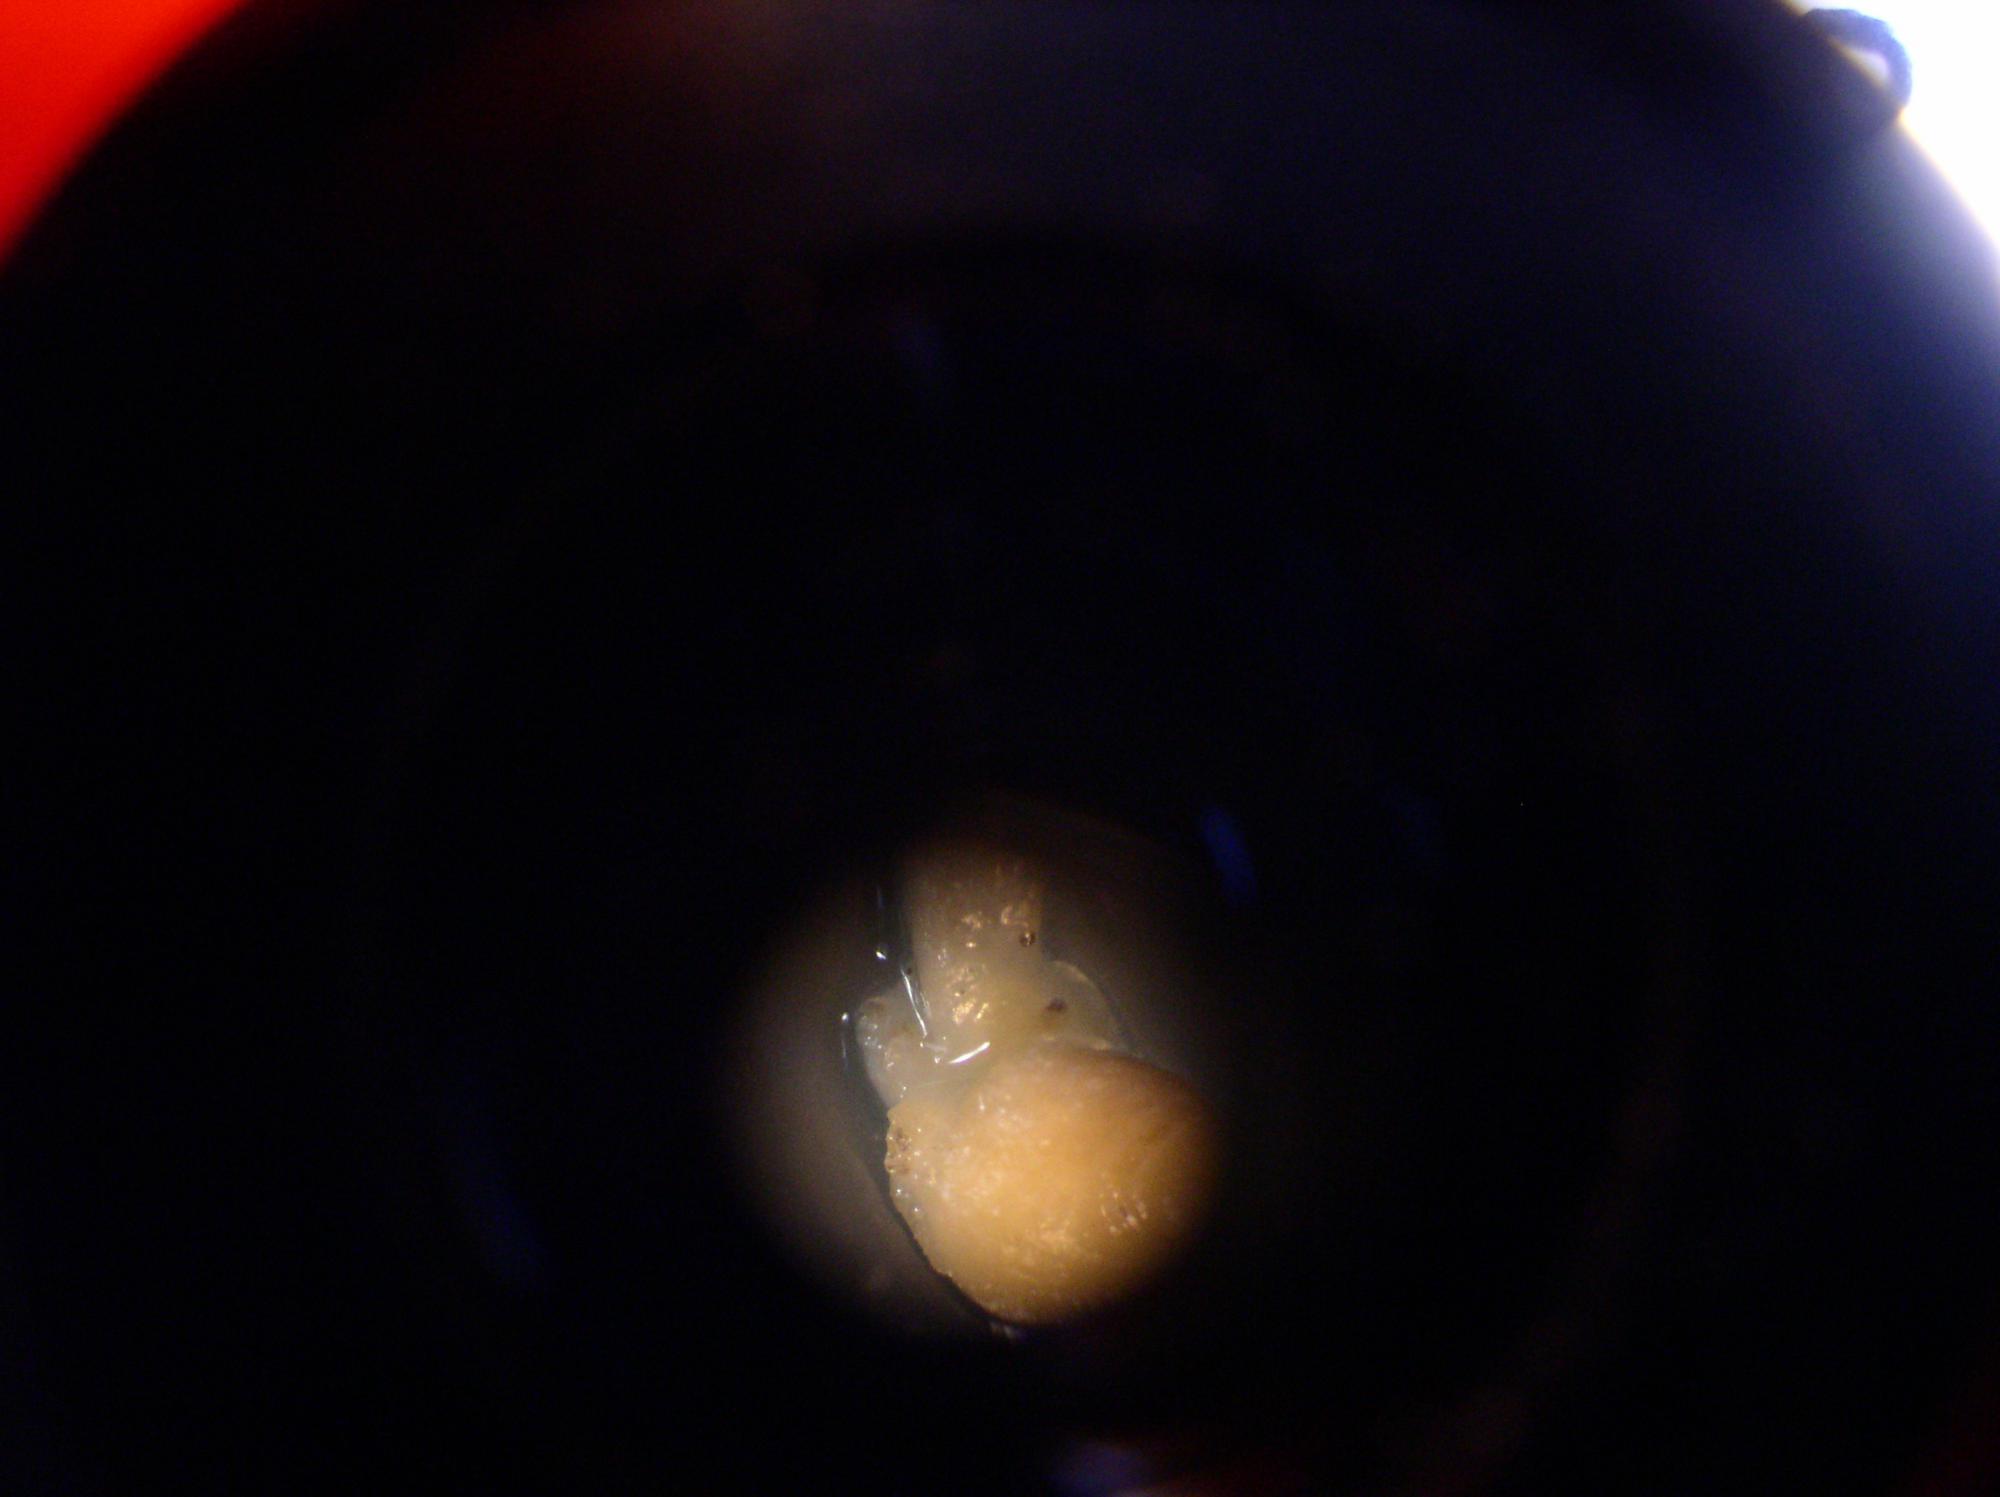

Вот фото, которые удалось сделать дома.

На фото:

1,2,6 - целые капсулы.

Они блестящие, покрыты некой плёнкой.

3-5 - разрезанные капсулы.

Внутренняя структура нопоминает мокрый хлебный мякиш.

В этом "мякише видны чёрные включения, как кусочки грязи.

Ещё одно фото.

Здесь видно, что у оставшегося самца Бальзани слева над глазом - какое-то повреждение кожи, а правее - белая точка.

Это такая же капсула, которая находится в воронкообразном углублении.

Потом капсула исчезнет, а углубление зарастёт.

Я наблюдала такое и раньше и думала, что это таким образом зарастают углубления.

LapkaLee, белая точка на последнем фото скорее всего сопутствующая гексамитозу дырочная болезнь которая как раз характерезуеться гнойниками